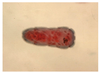

Chickens

Eimeria tenella

Major coccida of chickens

Infection of cecum

Note: Schizonts containing merozoites (bananas)

Chickens

Eimeria tenella

Chicken cecum

Note: bloody casts